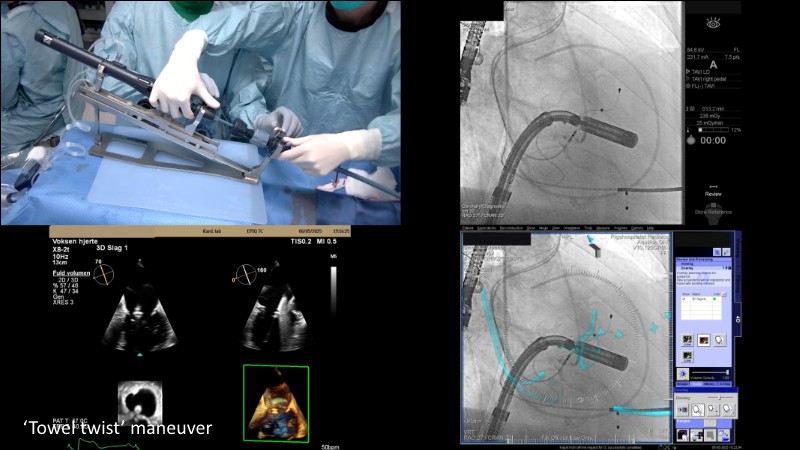

This EuroPCR 2025 session highlights the evolving role of transcatheter mitral valve replacement, focusing on the clinical potential of mitral regurgitation elimination. Get an overview of the current status of the Intrepid TMVR programme, learn about the transition to the 29Fr transfemoral system, and explore how patient screening—especially in the presence of mitral annular calcification—impacts procedural planning. Real-world case reviews from the APOLLO-EU trial offer practical insights into how this next-generation system is being applied in Europe today.